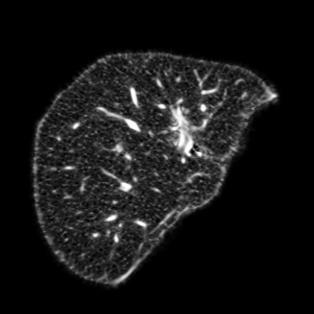

Manually segmenting the hepatic vessels from Computer Tomography (CT) is far more expertise-demanding and laborious than other structures due to the low-contrast and complex morphology of vessels, resulting in the extreme lack of high-quality labeled data. Without sufficient high-quality annotations, the usual data-driven learning-based approaches struggle with deficient training. On the other hand, directly introducing additional data with low-quality annotations may confuse the network, leading to undesirable performance degradation. To address this issue, we propose a novel mean-teacher-assisted confident learning framework to robustly exploit the noisy labeled data for the challenging hepatic vessel segmentation task. Specifically, with the adapted confident learning assisted by a third party, i.e., the weight-averaged teacher model, the noisy labels in the additional low-quality dataset can be transformed from "encumbrance" to "treasure" via progressive pixel-wise soft-correction, thus providing productive guidance. Extensive experiments using two public datasets demonstrate the superiority of the proposed framework as well as the effectiveness of each component.

翻译:将来自计算机地形学(CT)的肝脏船只人工分割,由于船只的低调和复杂形态,由于低调和复杂的形态,造成极端缺乏高质量的标签数据,因此比其他结构更需要专门知识和难度大得多。如果没有足够的高质量的说明,通常的数据驱动的基于学习的方法就会与不足的培训斗争。另一方面,直接引进低质量说明的额外数据可能会混淆网络,导致不良的性能退化。为了解决这一问题,我们提议建立一个新的、由教师协助的、有说服力的、有说服力的学习框架,为具有挑战性的肝脏船只分解任务强有力地利用响亮的标签数据。具体地说,在第三方(即加权平均教师模式)的协助下,经过变通的自信学习后,额外低质量数据集中的噪音标签可以从“阻力”转变为“压力”,通过渐进式的像素方法的软校正,从而提供富有成效的指导。使用两个公共数据集进行的广泛实验,显示了拟议框架的优越性以及每个组成部分的效能。